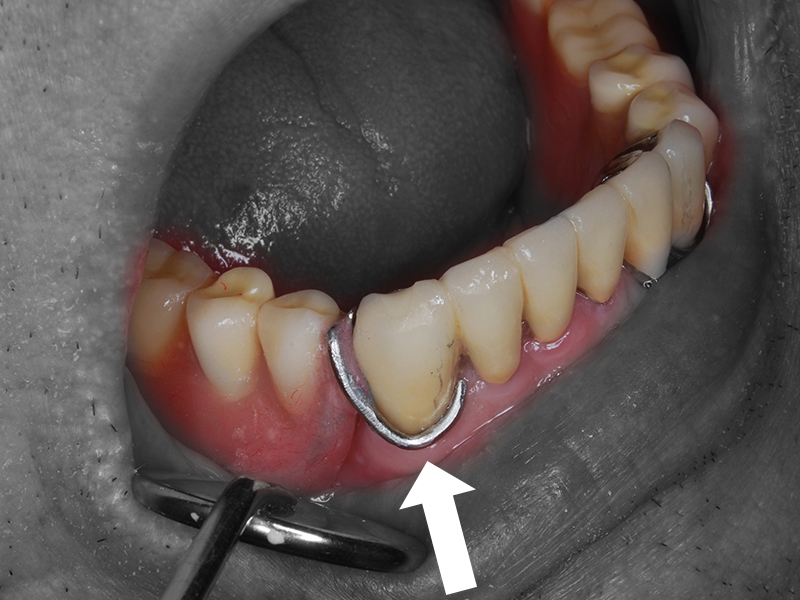

義歯維持装置(クラスプ)の欠けた部分

修理部分に凹みをつけ装着して型を取る

模型上で凹み部分にクラスプ新製

凹みの仮封鎖を取りクラスプ適合確認

義歯に組み込みレジンで固める

クラスプ修理の出来た義歯

修繕義歯の装着

通常の義歯修理は上の例のようにプラスチック部分に補強線や義歯の維持装置を組み込むことが殆どですが、金属の精密な義歯をお使いの場合は、現状を変えることなくレーザー溶接や高周波スポット溶接等も利用することがあります。